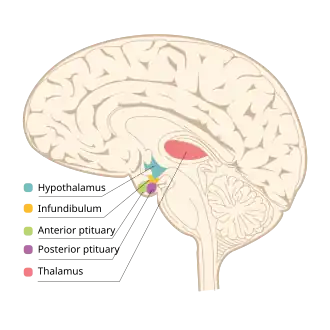

Location of the hypothalamus (cyan) in relation to the pituitary and to the rest of the brain | |

The hypothalamus (pl.: hypothalami; from Ancient Greek ὑπό (hupó) 'under' and θάλαμος (thálamos) 'chamber') is a small part of the vertebrate brain that contains a number of nuclei with a variety of functions. One of the most important functions is to link the nervous system to the endocrine system via the pituitary gland. The hypothalamus is located below the thalamus and is part of the limbic system.[1] It forms the basal part of the diencephalon. All vertebrate brains contain a hypothalamus.[2] In humans, it is about the size of an almond.[3]